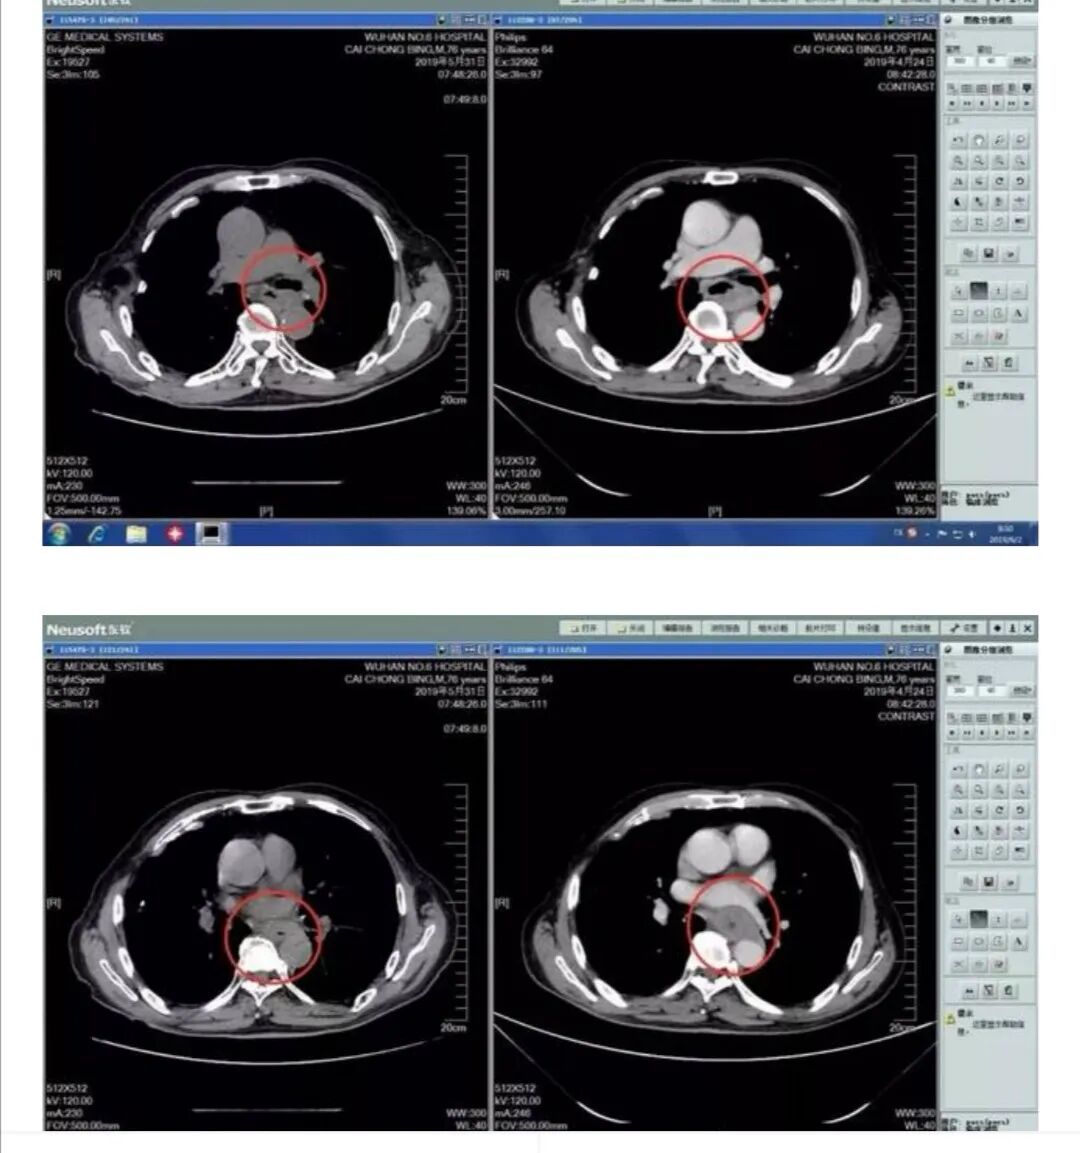

肿瘤科主任王国华表示,肿瘤科将继续开展与放射科联合读片活动,尽快提升肿瘤科医生和其它临床科室医生的读片水平,为肿瘤的临床诊断、疗效评估和放疗勾画靶区打下良好的影像学基础,他欢迎科室医生在临床工作中将收集到的病例与放射科医生共同学习、共同讨论、共同进步。